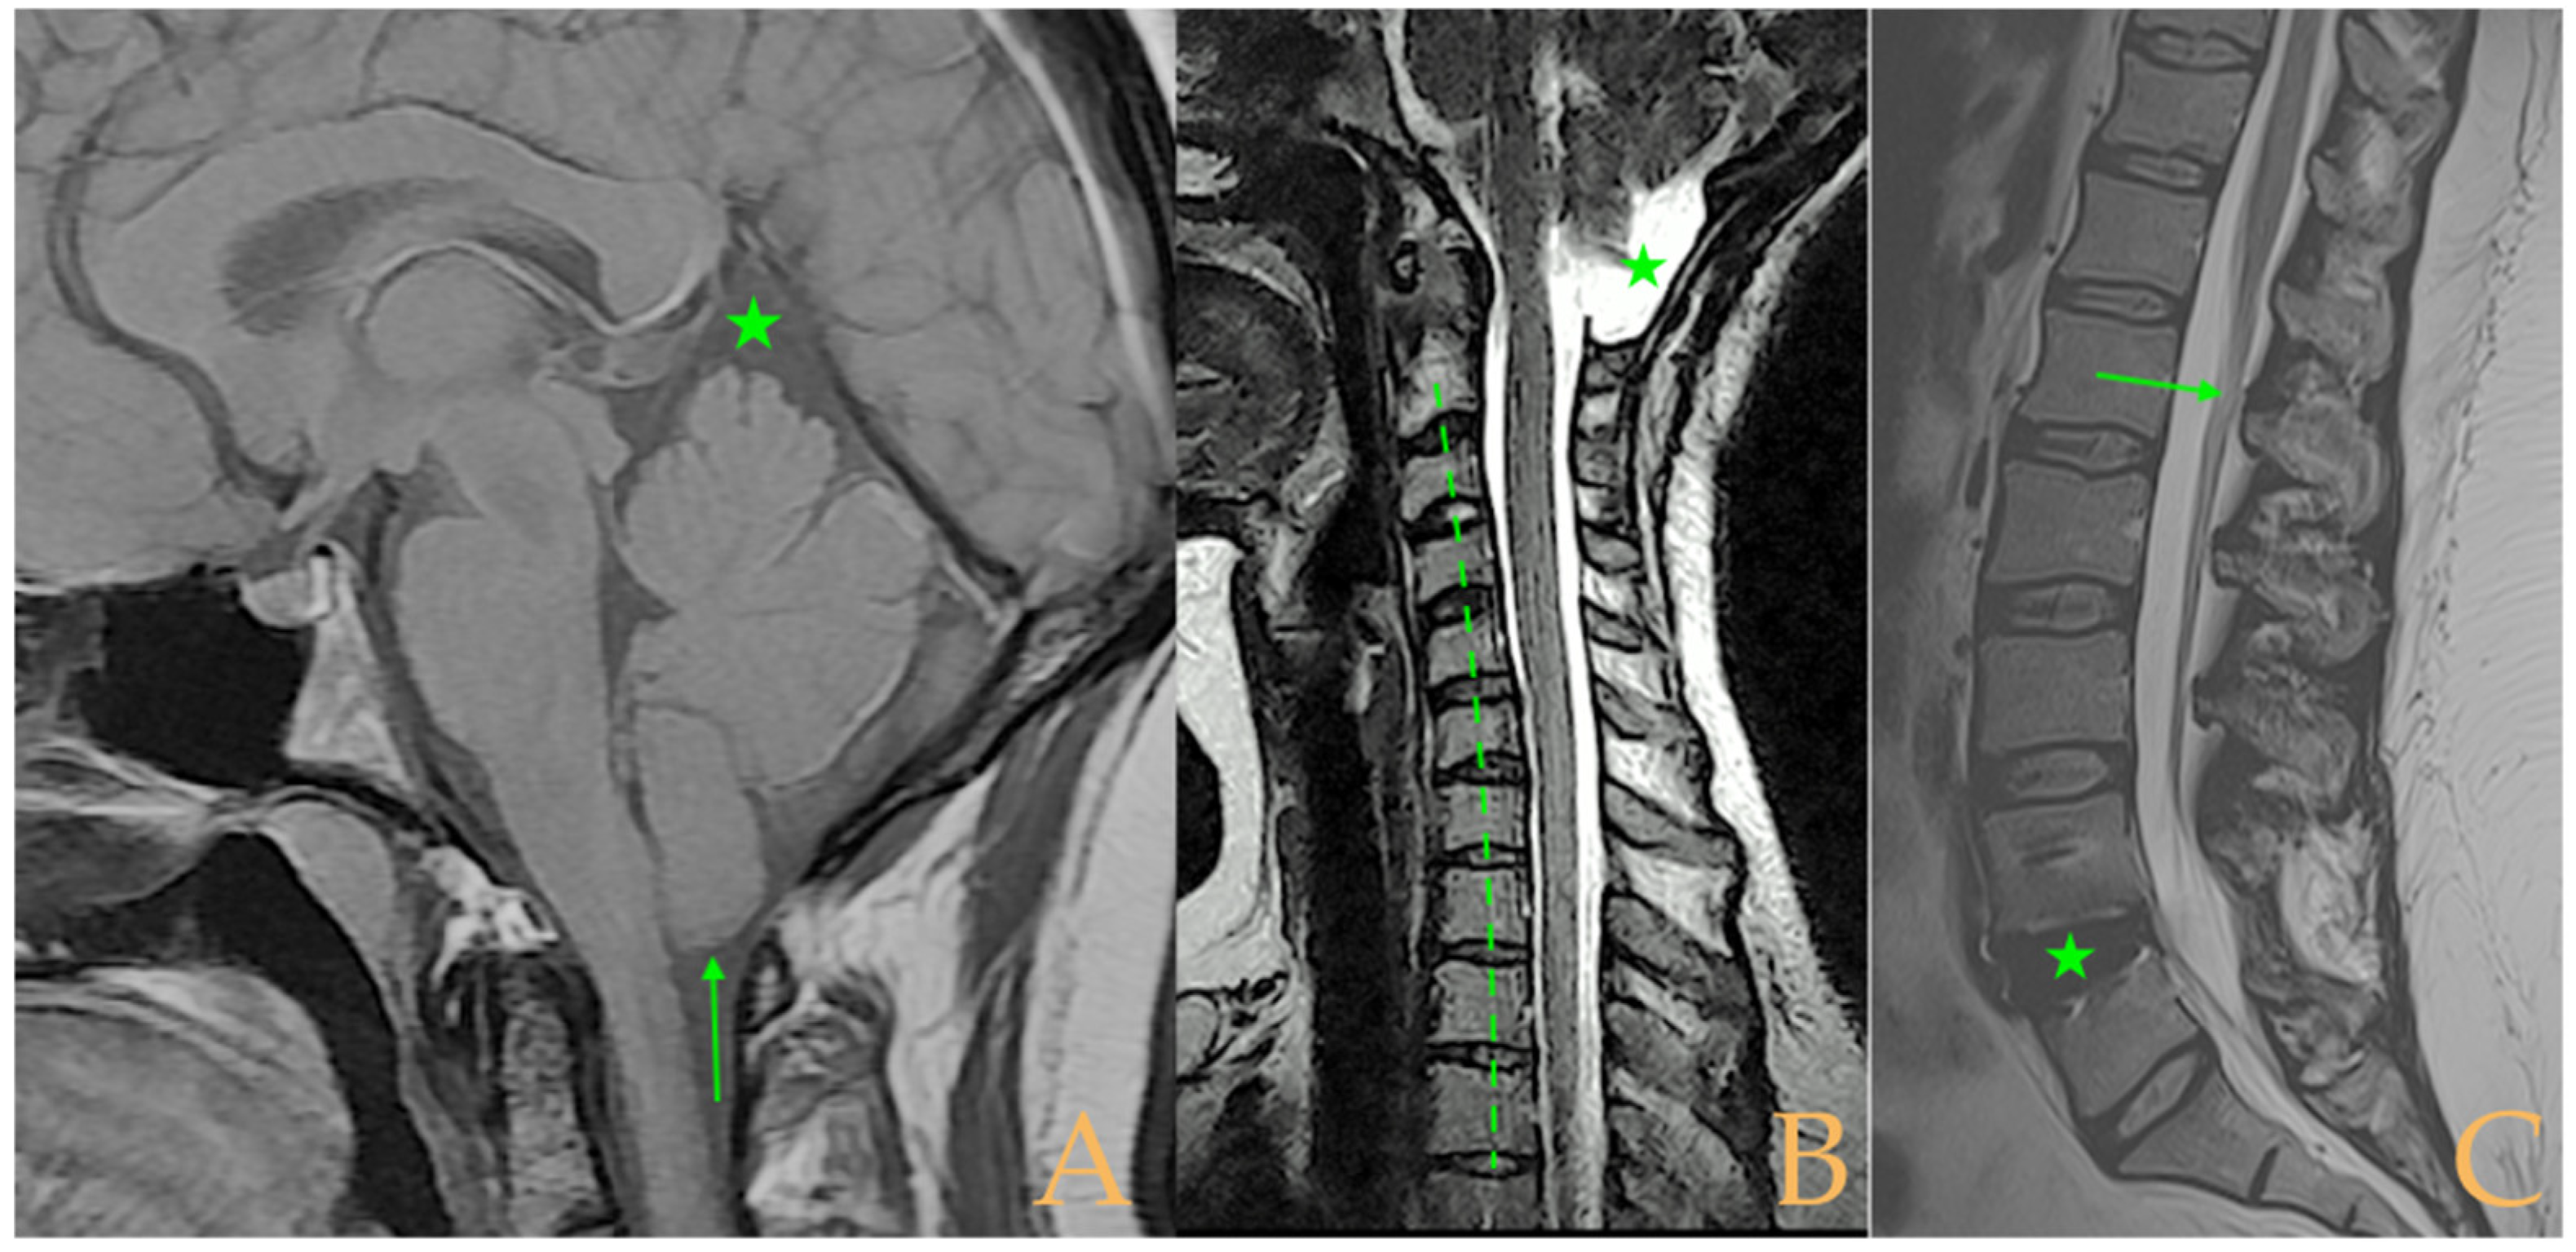

Figure 4.

Imaging of patient 4. A: Cranial MRI with visible descent of the cerebellar tonsils in the foramen magnum (stars); B: cervical MRI with straightening of the cervical spine (interrupted line) and cervical multiple disc disease (arrows); and C: lumbar MRI with conus medullaris at the upper third of L2 (arrow).

The MRI showed descent of the cerebellar tonsils, increased supracerebral space, and postsurgical repercussions of the sphenoid sinus in the right half. Empty sella turcica. Micro lacunae bilaterally in hemispheres, basal ganglia, and white matter. Straightening of the cervical spine. Cervical spinal cord with tense aspect and inferior lateral displacement, the thoracic portion appears tense with slight ischemia and oedema. Protrusions: C3-C4, C5-C6-C7, T7-T8, and L3-S1. Lumbar hyperlordosis. Sacrococcygeal hyperkyphosis. Ischemia and oedema in epiconus. Low conus medullaris at the level of the upper third of L2 vertebral body. Tarlov cyst at S2 (left) (Figure 4). Proximal filum terminale externum visible. Levoconvex lumbar scoliosis on the spine X-ray estimated at 6°; dextroconvex cervical and thoracic scoliosis estimated at 4°.